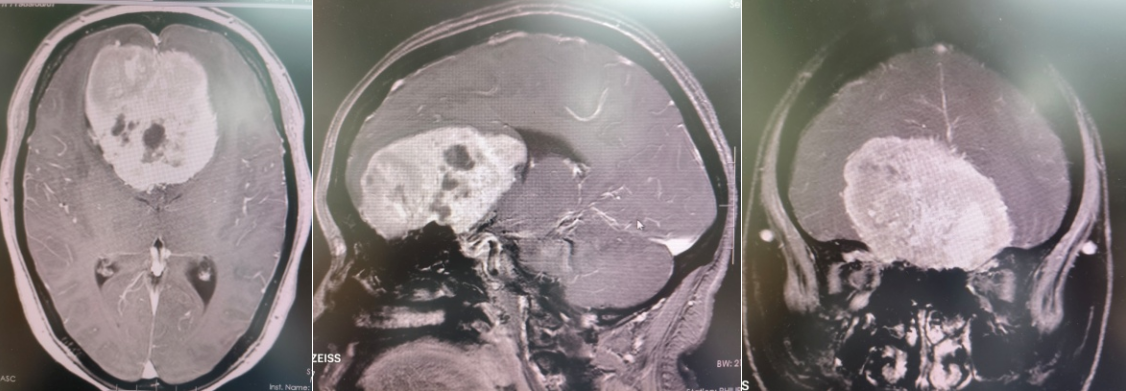

该患者突发剧烈头痛,持续一周未见缓解,经磁共振检查发现前颅窝底存在巨大占位性病变,初步诊断为嗅沟脑膜瘤。突如其来的重病让患者及家属陷入焦虑,而患者特殊的生理时期(产褥期)叠加高血压、先心病、肺动脉高压、贫血、低蛋白血症、电解质紊乱等多重基础疾病,手术风险极高。

术前